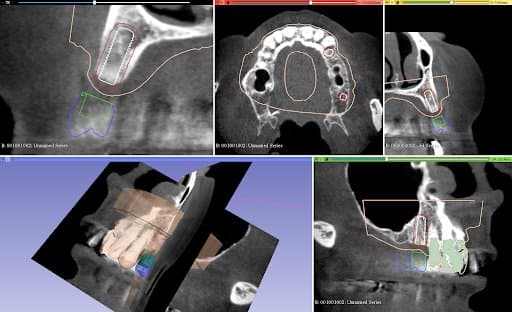

Planning of implant placement based on the CBCT

After the healing phase, a CBCT was taken to plan the implant placement and surgical technique. Due to the poor remaining bone volume and quality, it was decided to place the implants using a surgical guide to guarantee their accurate position in the areas where the bone quality was sufficient. Bone augmentation was discarded as a solution due to the complexity of this procedure for this specific clinical case. Alginate impressions were taken of both arches and sent to the dental laboratory, alongside the instructions for the implant positions, for design and fabrication of the surgical guide . A professional tooth cleaning was performed to prepare the oral cavity in a good hygienic condition for the operation.

Design Stage:

The plaster models were made from the impressions and digitized in Mr. Neubarth´s laboratory using a desktop scanner (Sirona InEos X5). The digital models could be superimposed with the CBCT (3D Accuitomo 170) in the software (Blender for dental). Artificial teeth were set up in the software and two implants of the appropriate length and diameter (Twinfit from Dentaurum) were imported.

After the final position of the implants was achieved and confirmed, the full arch surgical guide was designed considering the compatible guide sleeves.